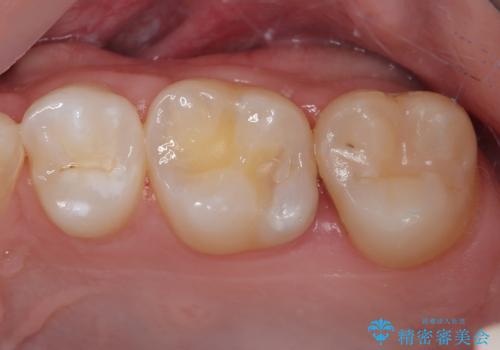

上顎左側第一大臼歯に齲蝕が認められたため、矯正治療終了後に 精度の高いセラミックインレー にて修復治療を行いました。